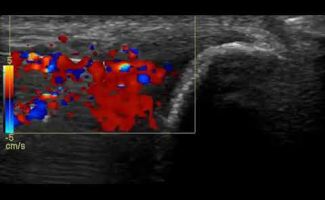

Η τεχνική PRP περιλαμβάνει τη λήψη μίας μικρής ποσότητας αίματος του ασθενούς, το οποίο φυγοκεντρείται ώστε να διαχωριστεί το πλάσμα που είναι πλούσιο σε αιμοπετάλια. Το προκύπτον πλάσμα εγχέεται, με την καθοδήγηση υπερήχου, στο σημείο της βλάβης.

Η καθοδήγηση υπερήχου κατά την ενέσιμη θεραπεία PRP αποτελεί κρίσιμο παράγοντα για την ακρίβεια και ασφάλεια της διαδικασίας.

Με τη δυνατότητα παρακολούθησης της βελόνας σε πραγματικό χρόνο, εξειδικευμένος Ιατρός-Ακτινολόγος μπορούν να καθορίσει με απόλυτη ακρίβεια την περιοχή όπου πρέπει να γίνει η ένεση. Αυτό εξασφαλίζει ότι η εισαγωγή του PRP θα γίνει ακριβώς στην επιθυμητή θέση, αποφεύγοντας γύρω ιστούς, νεύρα και αιμοφόρα αγγεία.

Η χρήση της υπερηχογραφίας όχι μόνο μειώνει τον κίνδυνο επιπλοκών, αλλά βελτιώνει και τα αποτελέσματα της θεραπείας, καθώς η ένεση διενεργείται με ακρίβεια στην πάσχουσα περιοχή, και όχι κατά προσέγγιση.